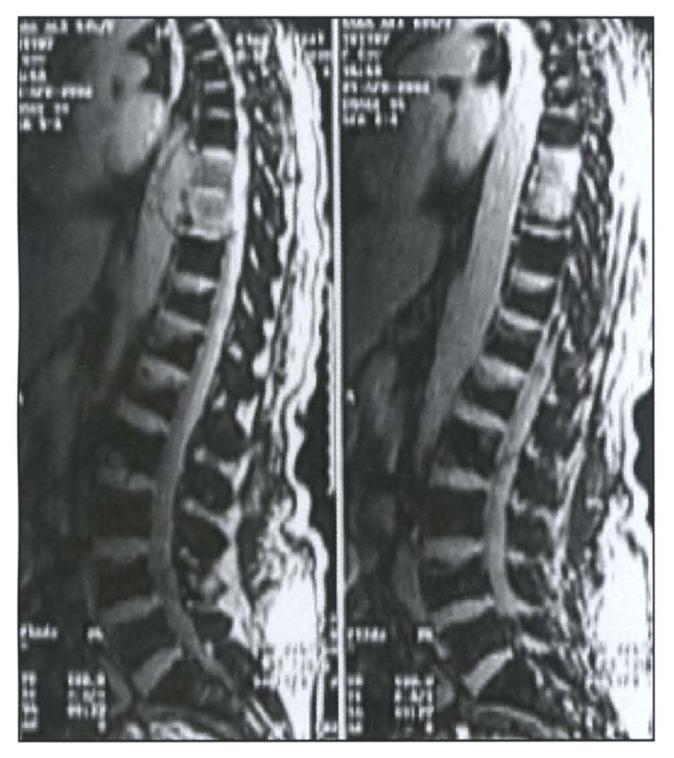

Metastatic hepatic carcinoid associated with ectopic ACTH syndrome, resistant to octreotide and ketoconazole therapy.

Ann Saudi Med. 2004 Sep-Oct;24(5):386-90. doi: 10.5144/0256-4947.2004.386.